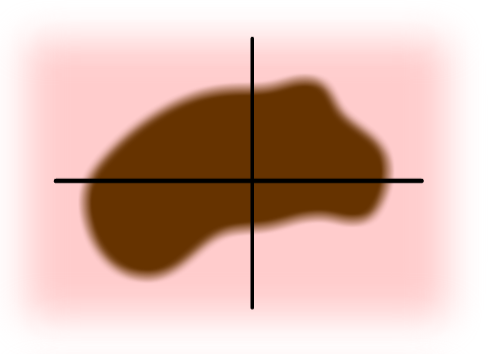

- A - Asymetrie - jedna polovina znaménka nevypadá jako druhá.

- B - Okraje (Borders) - jsou nepravidelné, zubaté nebo rozmazané.